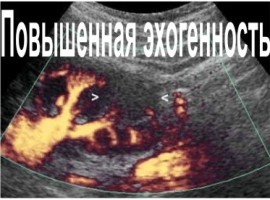

Повышенная эхогенность печени указывает на изменения в органе, такие как жировая инфильтрация, воспаление или фиброз. Эхогенность — это характеристика, определяемая при ультразвуковом исследовании, и ее изменения могут сигнализировать о необходимости дальнейшей диагностики. Эта статья разъяснит причины повышения эхогенности печени, возможные последствия и важность своевременного обращения к врачу для предотвращения серьезных заболеваний.

Повышенная эхогенность печени является значимым диагностическим показателем, который может указывать на различные заболевания этого органа. Врачи отмечают, что данный феномен часто связан с изменениями в тканевой структуре печени, такими как жировая дистрофия, фиброз или воспалительные процессы. При проведении ультразвукового исследования повышенная эхогенность может указывать на наличие жировых отложений, что характерно для неалкогольной жировой болезни печени.

Эхогенность может быть умеренно снижена или повышена. Высокая скорость отражения характерна для костной ткани, воспалённых внутренних органов и тканей, имеющих большое количество жировых клеток (например, при жировом перерождении печеночной ткани).

УЗИ – это один из самых безопасных и безболезненных методов диагностики внутренних органов. Результаты, полученные в ходе эхографии, помогают выявить различные отклонения. Во время исследования пораженного органа можно оценить степень и скорость отражения ультразвуковых волн от тканей.

Несмотря на то, что звучит это слово довольно пугающе, при выявлении повышенной эхогенности не стоит сразу придумывать себе какие-либо тяжелые заболевания. Эхогенная плотность – важный показатель при проведении исследования. Говоря проще, это способность отражать звук, который затем обрабатывается в картинку. Ее-то мы и можем видеть на экране во время ультразвукового исследования. Повышенная эхогенность говорит о том, что ткани отражают звук очень хорошо (на экране они выглядят как светлые участки).